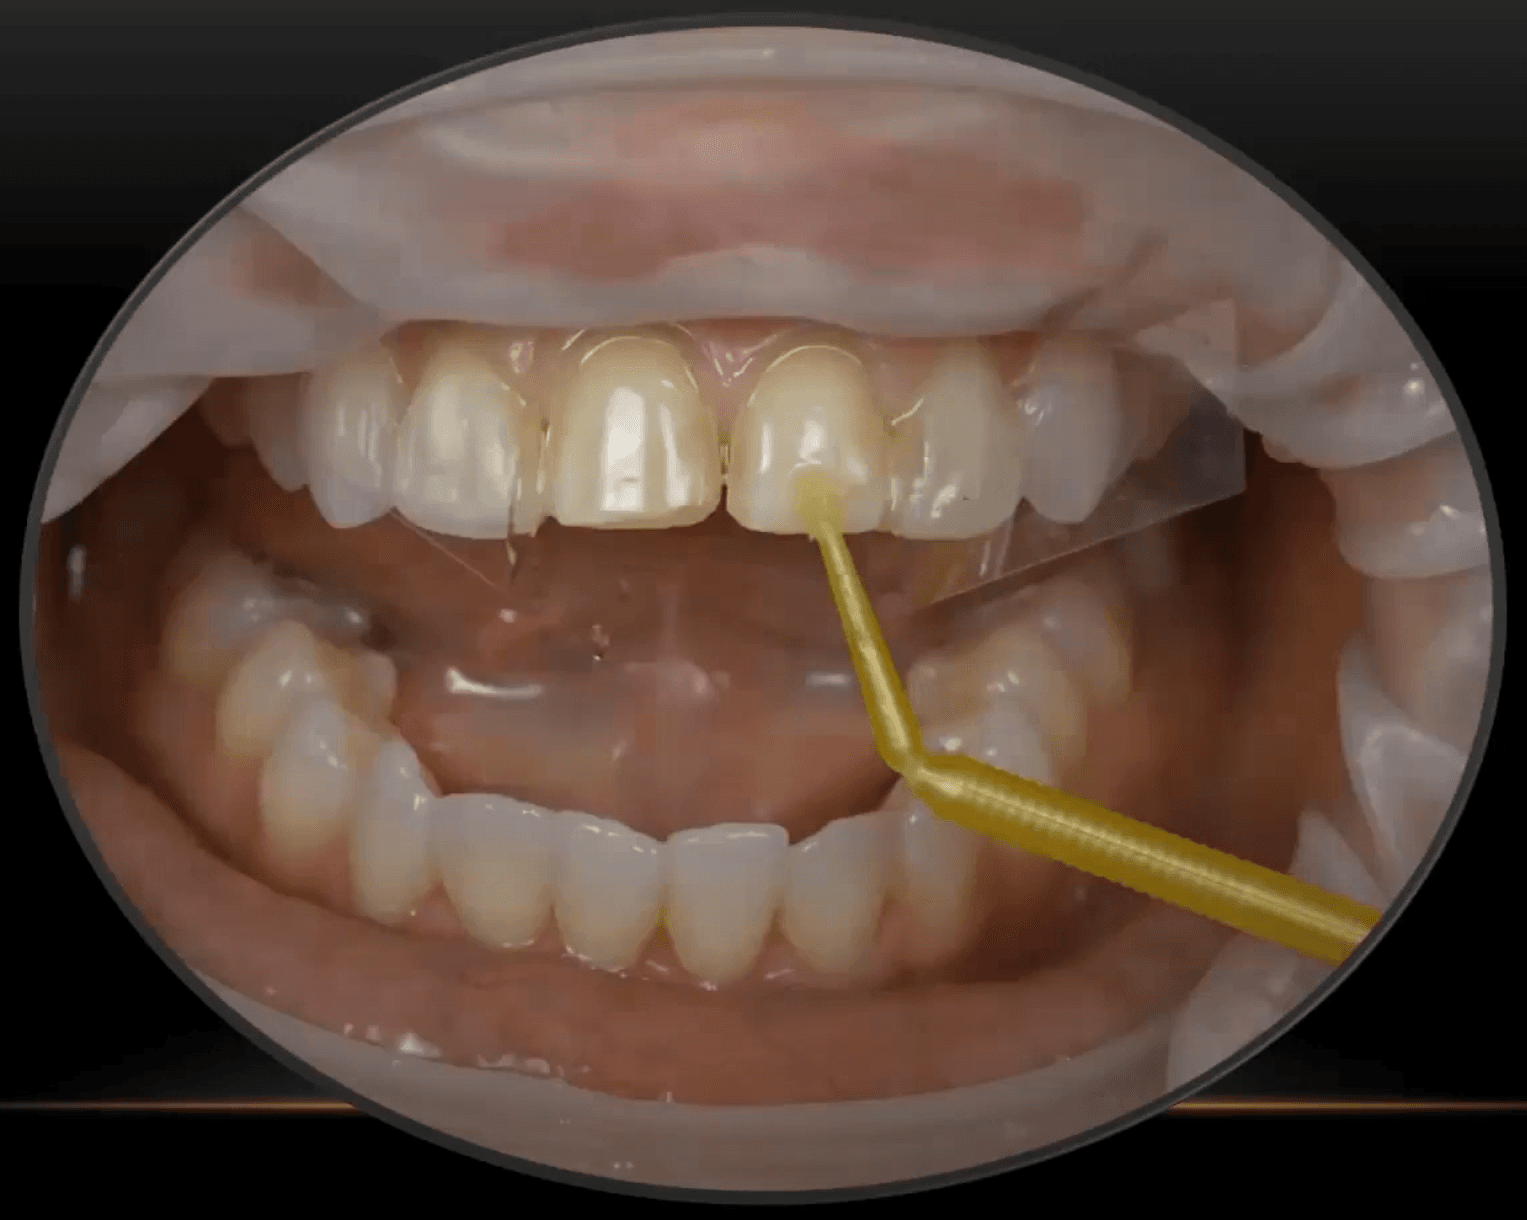

A Proven Approach for Veneer Cementation

When it comes to veneers, many will agree that the cementation process is the scariest part. There’s a lot of room for error here, so how can you ease the press...